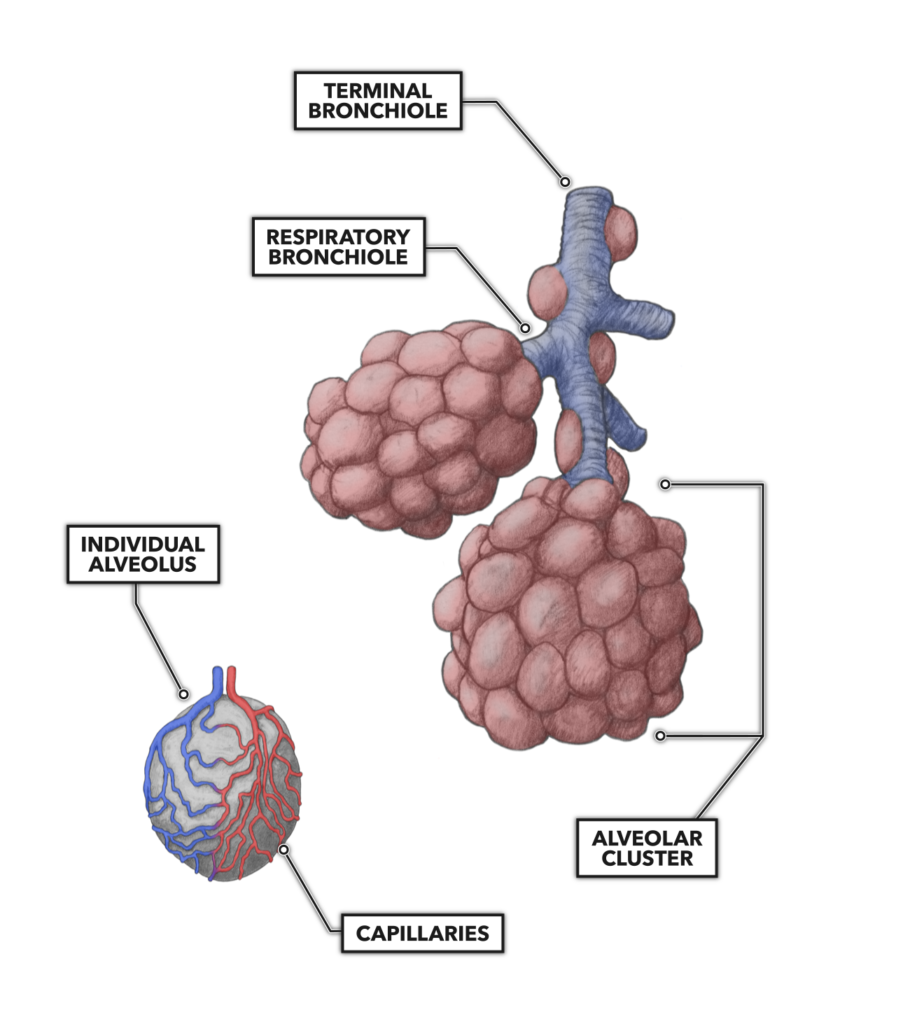

CrossFit | Lung Anatomy: The Airway And Alveoli

www.crossfit.com

www.crossfit.com

alveoli lung bronchioles clusters adjacent crossfit airway alveolus capillaries packed densely terminus buttress